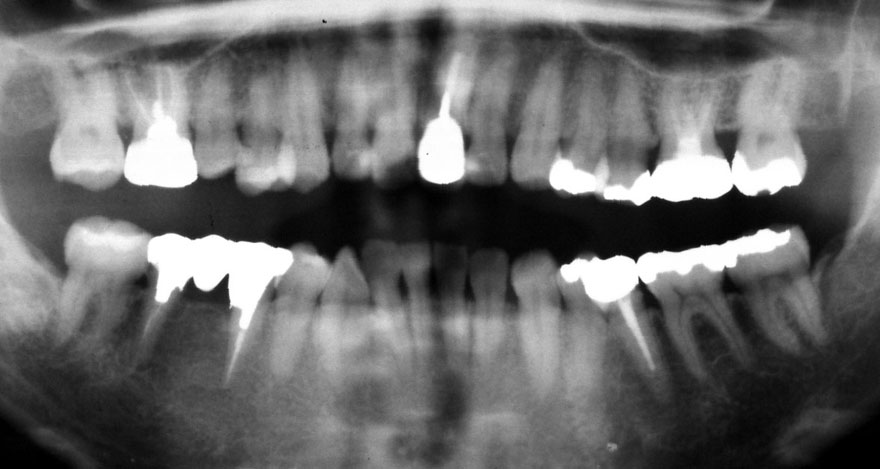

初診時 28歳 男性 平均歯槽骨喪失量:2.35mm

河田歯科医院

30年後 58歳

平均歯槽骨喪失量:3.88mm

22年間喪失量:-1.53mm

年間喪失速度:-0.05mm

(ケア頻度:2.80ヵ月ごと)